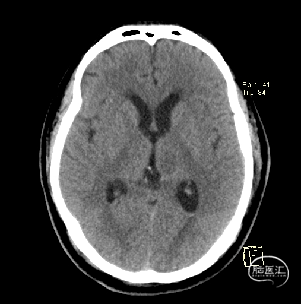

术后当天CT

术后1周CT复查